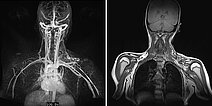

Dynamische, kontrastmittelunterstützte, zeitlich hochaufgelöste MR-Angiographie 5 Tage nach Embolisation; Darstellung in der Spätphase 107 s nach intravenöser Kontrastmittelapplikation. Auch nach diesem langen Delay zeigt sich keine Restperfusion der arteriovenösen Malformation mehr. Lediglich einige nicht verschlossene arterielle Zuflüsse sind noch dargestellt, diese finden jedoch keinen Abstrom oder Anschluss an die AVM mehr.

Dynamische, kontrastmittelunterstützte, zeitlich hochaufgelöste MR-Angiographie (linkes Bild) 5 Tage nach offener Resektion des verschlossenen Nidus; Darstellung wiederum in der Spätphase 107 s nach intravenöser Kontrastmittelapplikation. Auch nach diesem langen Delay zeigt sich keine Restperfusion der arteriovenösen Malformation mehr. Der initial in der koronaren, T1-gewichteten, nativen MRT (rechtes Bild) vormalig noch sichtbare Raumforderungseffekt der AVM ist nach der Resektion verschwunden.